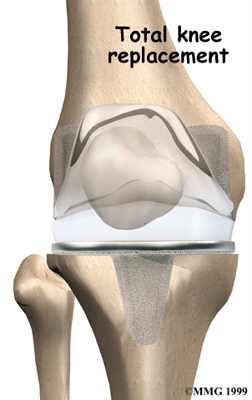

Artificial Knee Replacement

An artificial knee replacement is the ultimate solution for advanced knee OA.

Surgeons prefer not to put a new knee joint in patients younger than 60. This is because younger patients are generally more active and might put too much stress on the joint, causing it to loosen or even crack. A revision surgery to replace a damaged prosthesis is harder to do, has more possible complications, and is usually less successful than a first-time joint replacement surgery.

Related Document: FYZICAL Waterford's Guide to Artificial Joint Replacement of the Knee